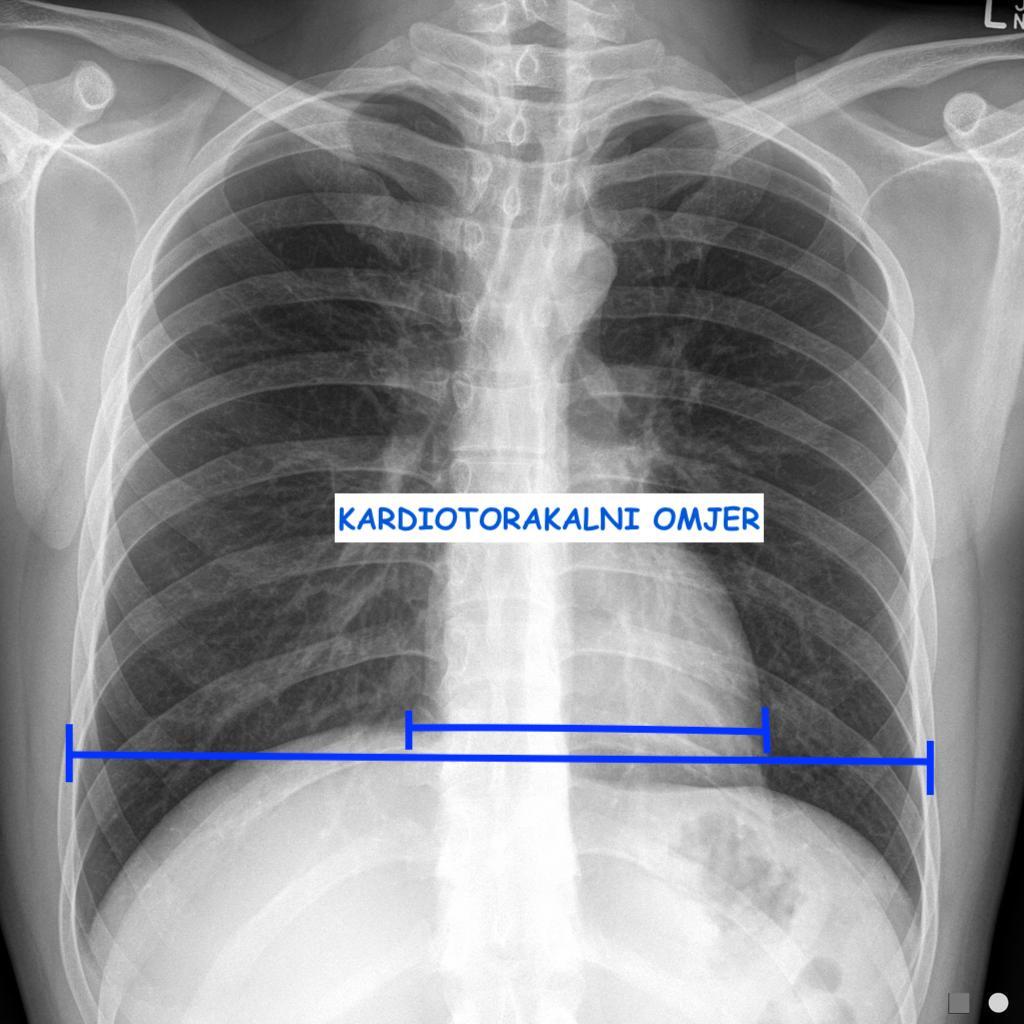

Analiza RTGa započinje uvidom u stanje mekih tkiva i koštanih elemenata grudnog koša, da bi otklonili sumnju na potkožni emfizem ili eventualno neku patologiju rebara. Gledamo simetriju plućnih polja sa desne i sa lijeve strane, poredimo vrhove pluća koji također moraju biti simetrični, položaj traheje i njene bifurkacije (može biti pomjerena udesno zbog aorte koja jaše iznad desnog principalnog bronha), te centralnu medijastinalnu sjenu. Pažnju posebno treba obratiti na hiluse(naročito na limfne čvorove ako su uvećani - sarkoidoza), kakvog su izgleda (transparencije), plućnu vaskularnu šaru koja polazi iz hilusa, zatim kardiofrenični i kostofrenični ugao (fiziološki oštri i transparentni, bez sadržaja. Kardiofrenični ugao može biti zasjenjen u inspiriju v. cavom inferiror i hepatičnim venama). Mjerimo kardio-torakalni omjer koji predstavlja razliku između u utrašnjeg dijametra toraksa i vanjskog dijametra srca. Normalan KT omjer iznosi 1/3 tj. srce zauzima 1/3 ukupnog dijametra toraksa. KT omjer veći od 0.75 je mogući znak kardiomegalije. Potrebno je analizirati desnu i lijevu konturu centralne medijastinalne sjene i opisati eventualne promjene.